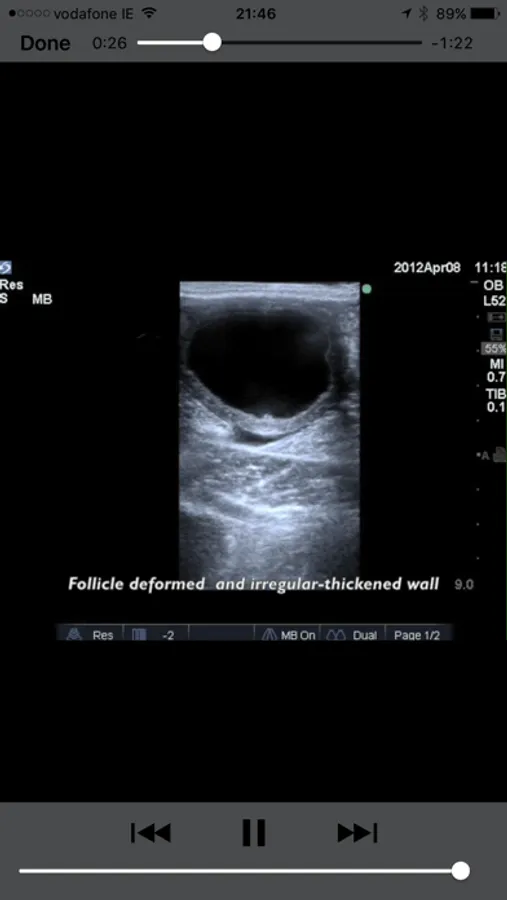

Equine reproductive ultrasound is a comprehensive guide to the examination of the equine female reproductive tract. It features high quality labeled pictures clearly demonstrating the important structures. Furthermore, every phase and condition discussed features high quality ultrasound video loops. All of the pictures and videos are on the phone or iPad and no internet connection is required after the first use.

Developed by Dr Marco Livini, past coordinator of SIRE (Italian Society of Equine Reproduction) and past President of SIVE (Italian Society of Equine Practitioners), the App provides extensive notes, still ultrasonographic images and videos.

•Estrus or follicular phase